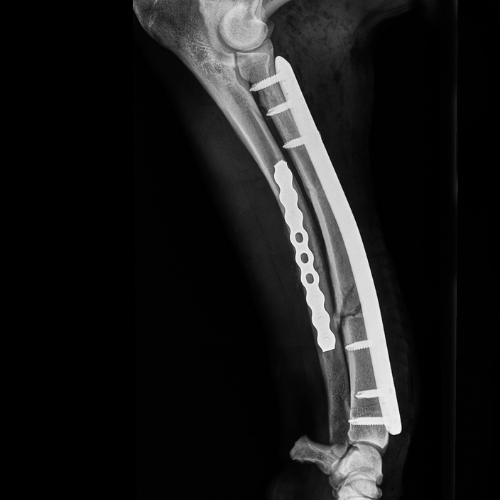

El servicio de traumatología está dirigido por Enrique Senís, especialista en traumatología y ortopedia por la Universidad Complutense de Madrid . Estamos orientados al diagnóstico y tratamiento de patologías del sistema musculoesquelético, incluyendo fracturas, luxaciones, rotura de ligamento cruzado y demás alteraciones articulares y deformidades óseas.

Disponemos de medios diagnósticos avanzados y aplicamos técnicas quirúrgicas de última generación en osteosíntesis, estabilización articular y corrección de deformidades, con el objetivo de restaurar la funcionalidad y minimizar el dolor en nuestros pacientes.